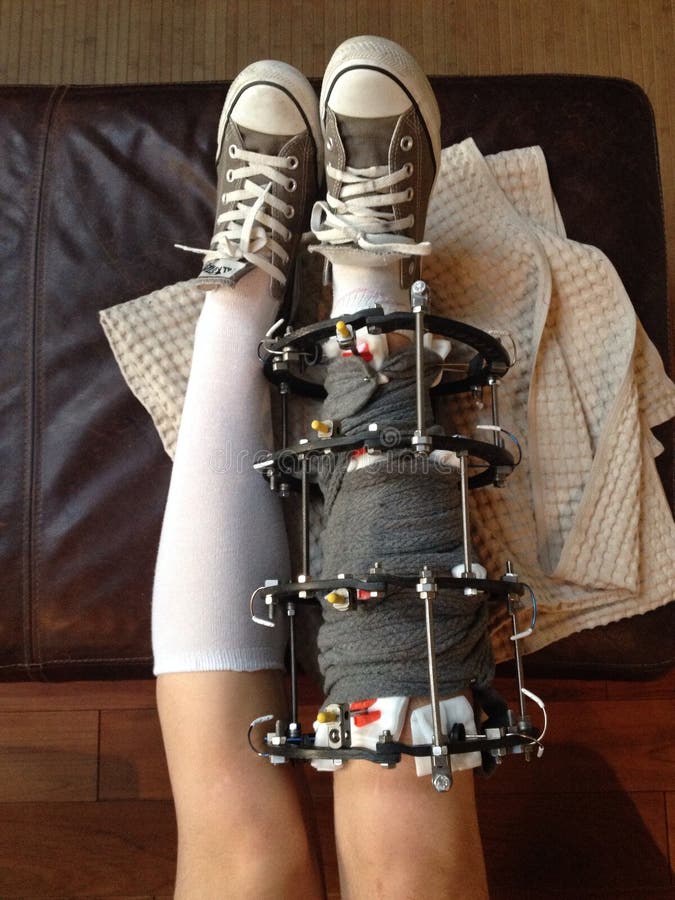

Аппарат Илизарова: принцип работы и применение

Раздел: Моменты озарения